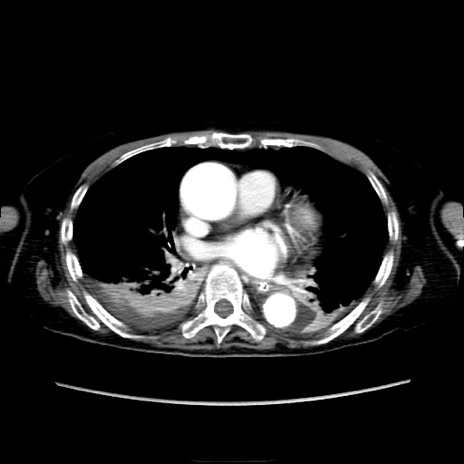

症例40(横断像)

【症例】90歳代女性

【主訴】腹痛・嘔吐

【現病歴】 食欲低下、嘔吐があり昨日他院受診。肺炎と診断され入院となる。入院後より腹部全体に圧痛あり。胃管留置され経過みていたが、症状持続するため、

当院転院となる。

【既往歴】胸椎圧迫骨折、胆石症

【身体所見】腹部:中央に激痛あり、圧痛あり、反跳痛不明

【データ】WBC 17100、CRP 18.82

横断像